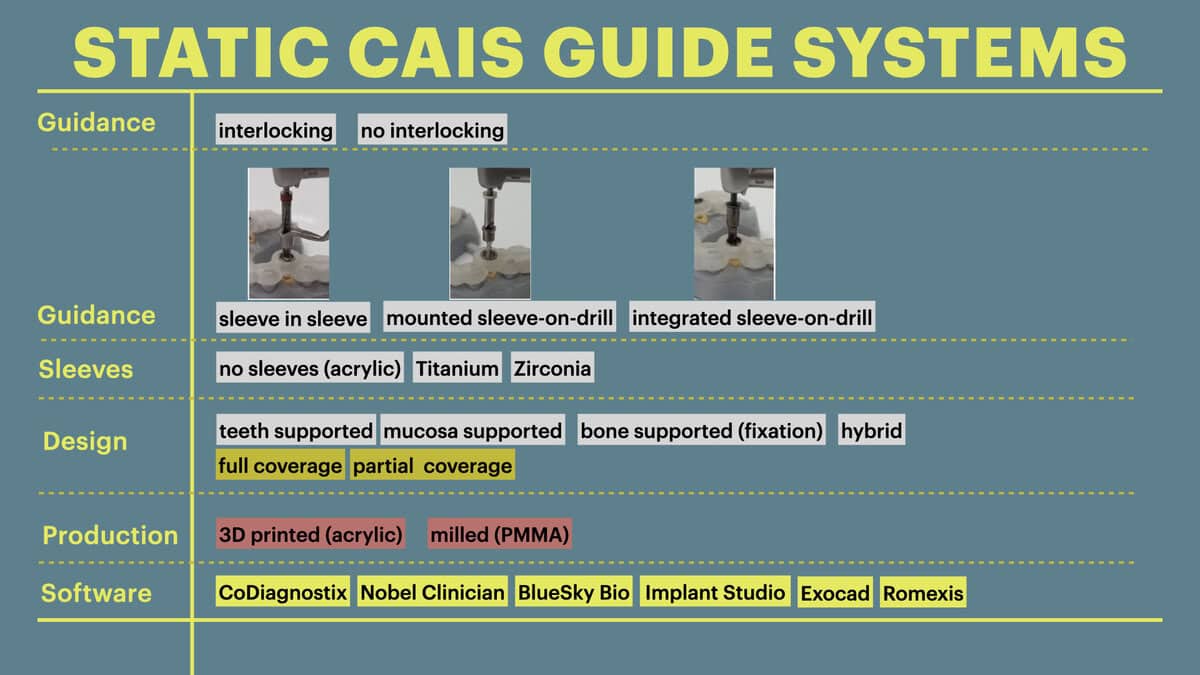

The static CAIS technology

The main idea behind the static CAIS is rather simple: create an acrylic “template”, which will guide our drills to the perfect osteotomy and then place the implant accordingly. It is based therefore on a 3D printed surgical guide with “sleeves”, which allow the placement of the drills controlling angle and position and “stops” to control the depth. The guide can be supported on teeth, on oral mucosa, on the underlying bone through mini screws or a combination of the previous. It can be a single piece guide, or “stackable” in order to cover several procedures, such as for example a possible ostectomy prior to implant placement or a lateral sinus floor augmentation. But this is about where the principle ends and the application starts! Today almost every major implant brand has its own guided surgery software, instruments and overall protocol (Figure 2). The differences can be significant and this diversity is not based on evidence, but rather reflects each company’s philosophy, design, historical features and insider-view on implant surgery. Does it really matter? Well, evidence shows that it does. In a recent study we compared the precision of implant placement with 5 different commonly available guide designs and guided surgery configurations (3). The results showed significant differences, with the “sleeve in sleeve” guides achieving almost half the deviation than some of the “mounted” or “integrated” sleeve guides (Figure 2). At the same time, accuracy might be not the only parametre that is clinically important in a system. Ease of use by the surgeon, reliability of the full workflow, availability of a wide array of drills, sizes and components, durability and costs are also to be accounted for. As we begin to understand the implication of design parametres through proper research, guided surgery kits in the future might start to converge towards the best practices or principles which deliver the most. For now however, be mindful, there is not one such think as “static guided surgery protocol”, despite what some systematic reviews will try to convince you. On the contrary, there are many different protocols, with significant differences in results, potential and limitations. Choose wisely!